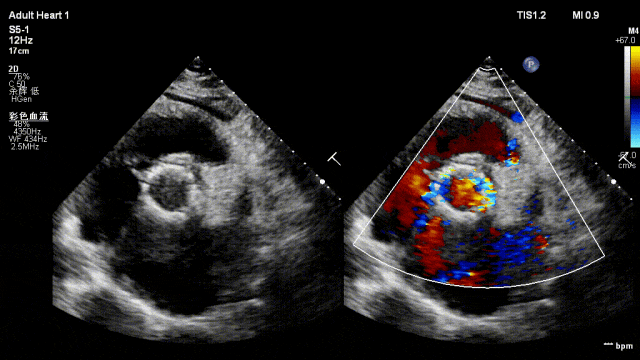

其中,主动脉瓣膜位于左心室和主动脉之间,是心脏血液循环最重要的“阀门”。主动脉瓣这个阀门发生狭窄或关闭不全,就会导致血液返流,引起左心室扩大,心脏逐渐出现动力不足甚至功能衰竭,患者会出现胸闷、憋气、胸痛,严重者会发生猝死。该类型高龄患者最佳选择是通过经导管主动脉瓣置换术(TAVR)微创介入手术治疗。但由于老伯是超大瓣环,瓣膜尺寸不足、锚定力不够,导致无法常规开展该术式。

术前主动脉根部造影:可见主动脉瓣大量反流,左心室扩大

术后4天,主动脉瓣膜植入后反流明显改善,瓣膜植入效果好,锚定器械无位移。